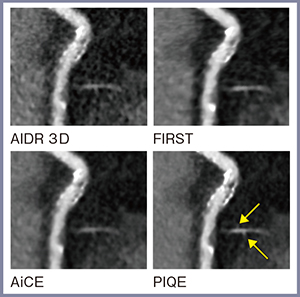

3.ファントム画像の視覚評価

図3に,ファントムの冠動脈の模擬狭窄部分のcurved MPR(CPR)画像を示す。FIRST(図3 b)では空間分解能に優れた画像が,AiCE(c)では非常にノイズの少ない画像が得られているが,PIQE(d)では高空間分解能とノイズ抑制を両立した画像が得られており,狭窄部分の血管内腔を良好に視認できる。また,FOV 100mmにすることで,さらに空間分解能が向上する(図3 e)。また,従来画像再構成法では狭窄部分はパーシャルボリューム効果によりCT値がやや低下しているが,PIQEではCT値が低下することなく描出されている。

図3 模擬狭窄のCPR画像

同症例のCPR画像でソフトプラークによる約50%狭窄がある部分を拡大すると,PIQEではほかの再構成法と比較して,内腔とプラークの境界が明瞭に描出されていることがわかる(図5)。また,右側に分枝が確認できるが,PIQEでは分枝からさらに分岐する細い血管(←)も描出されており,PIQEが微細血管の描出においても有用であることがわかる。